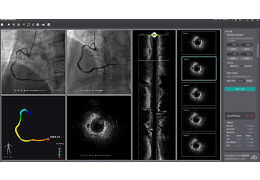

成像智能。

Eclipse 成像智能功能提供强大的处理能力和最佳质量的影像,同时减少质量错误并提高剂量效率。

凭借 AI、专有算法和先进的影像处理能力,提供出色的影像质量和无与伦比的诊断信心。

与标准影像处理相比,智能降噪功能可使客户降低辐射剂量,而不会损失影像质量。这在新生儿和儿科成像中尤其重要,在这种情况下以尽可能低的剂量成像至关重要。

提供相配视图选项,以减少所需的曝光次数,并提供更清晰的感兴趣区域视图。